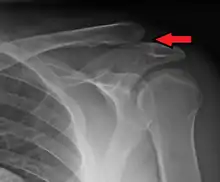

An Xray showing a separated shoulder. Notice the separation between the end of the collarbone and the scapula.

X-ray indicates a separated shoulder when the acromioclavicular joint space is widened (it is normally 5 to 8 mm).[8]